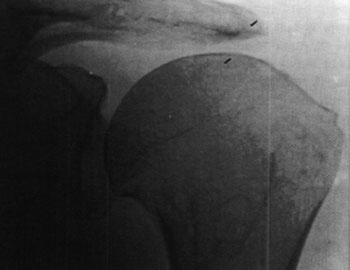

Figura III:

Radiografía de hombro de frente, muestra ascenso de la cabeza humeral en relación a la cavidad glenoidea y fricción acromial. Se interpreta como lesión de la porción larga del bíceps y masiva del manguito rotador.